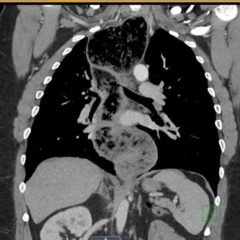

The patient’s lab work was significant for an elevated Troponin T of 0.03 ng/mL (normal ≤ 0.02 ng/mL), suggestive of right heart strain. The diagnosis of pulmonary embolism was confirmed on CT angiogram of the chest, which revealed large filling defects in the right and left pulmonary arteries extending into their respective segmental branches. Upon confirmation of the diagnosis, the patient was taken for emergent endovascular catheter-directed tissue plasminogen activator (tPA) and was subsequently admitted to the medical intensive care unit. She had an inferior vena cava (IVC) filter placed after five days and was discharged from the hospital seven days after admission.